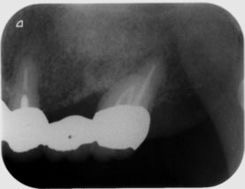

インプラント1本埋入のケースでも事前にCTシミュレーションを行い、副鼻空との関係や、下顎臼歯部なら下顎管との距離や補綴する歯との位置関係を把握します。

シビアなケースでは1本でもサージガイドを作製するなど安心安全なインプラント治療を行っています。

右下1本インプラント埋入した症例

ソケットリフトにより骨造成を行った症例

サイナスリフトにより上顎洞の横から

骨に穴を開け骨造成を行った症例